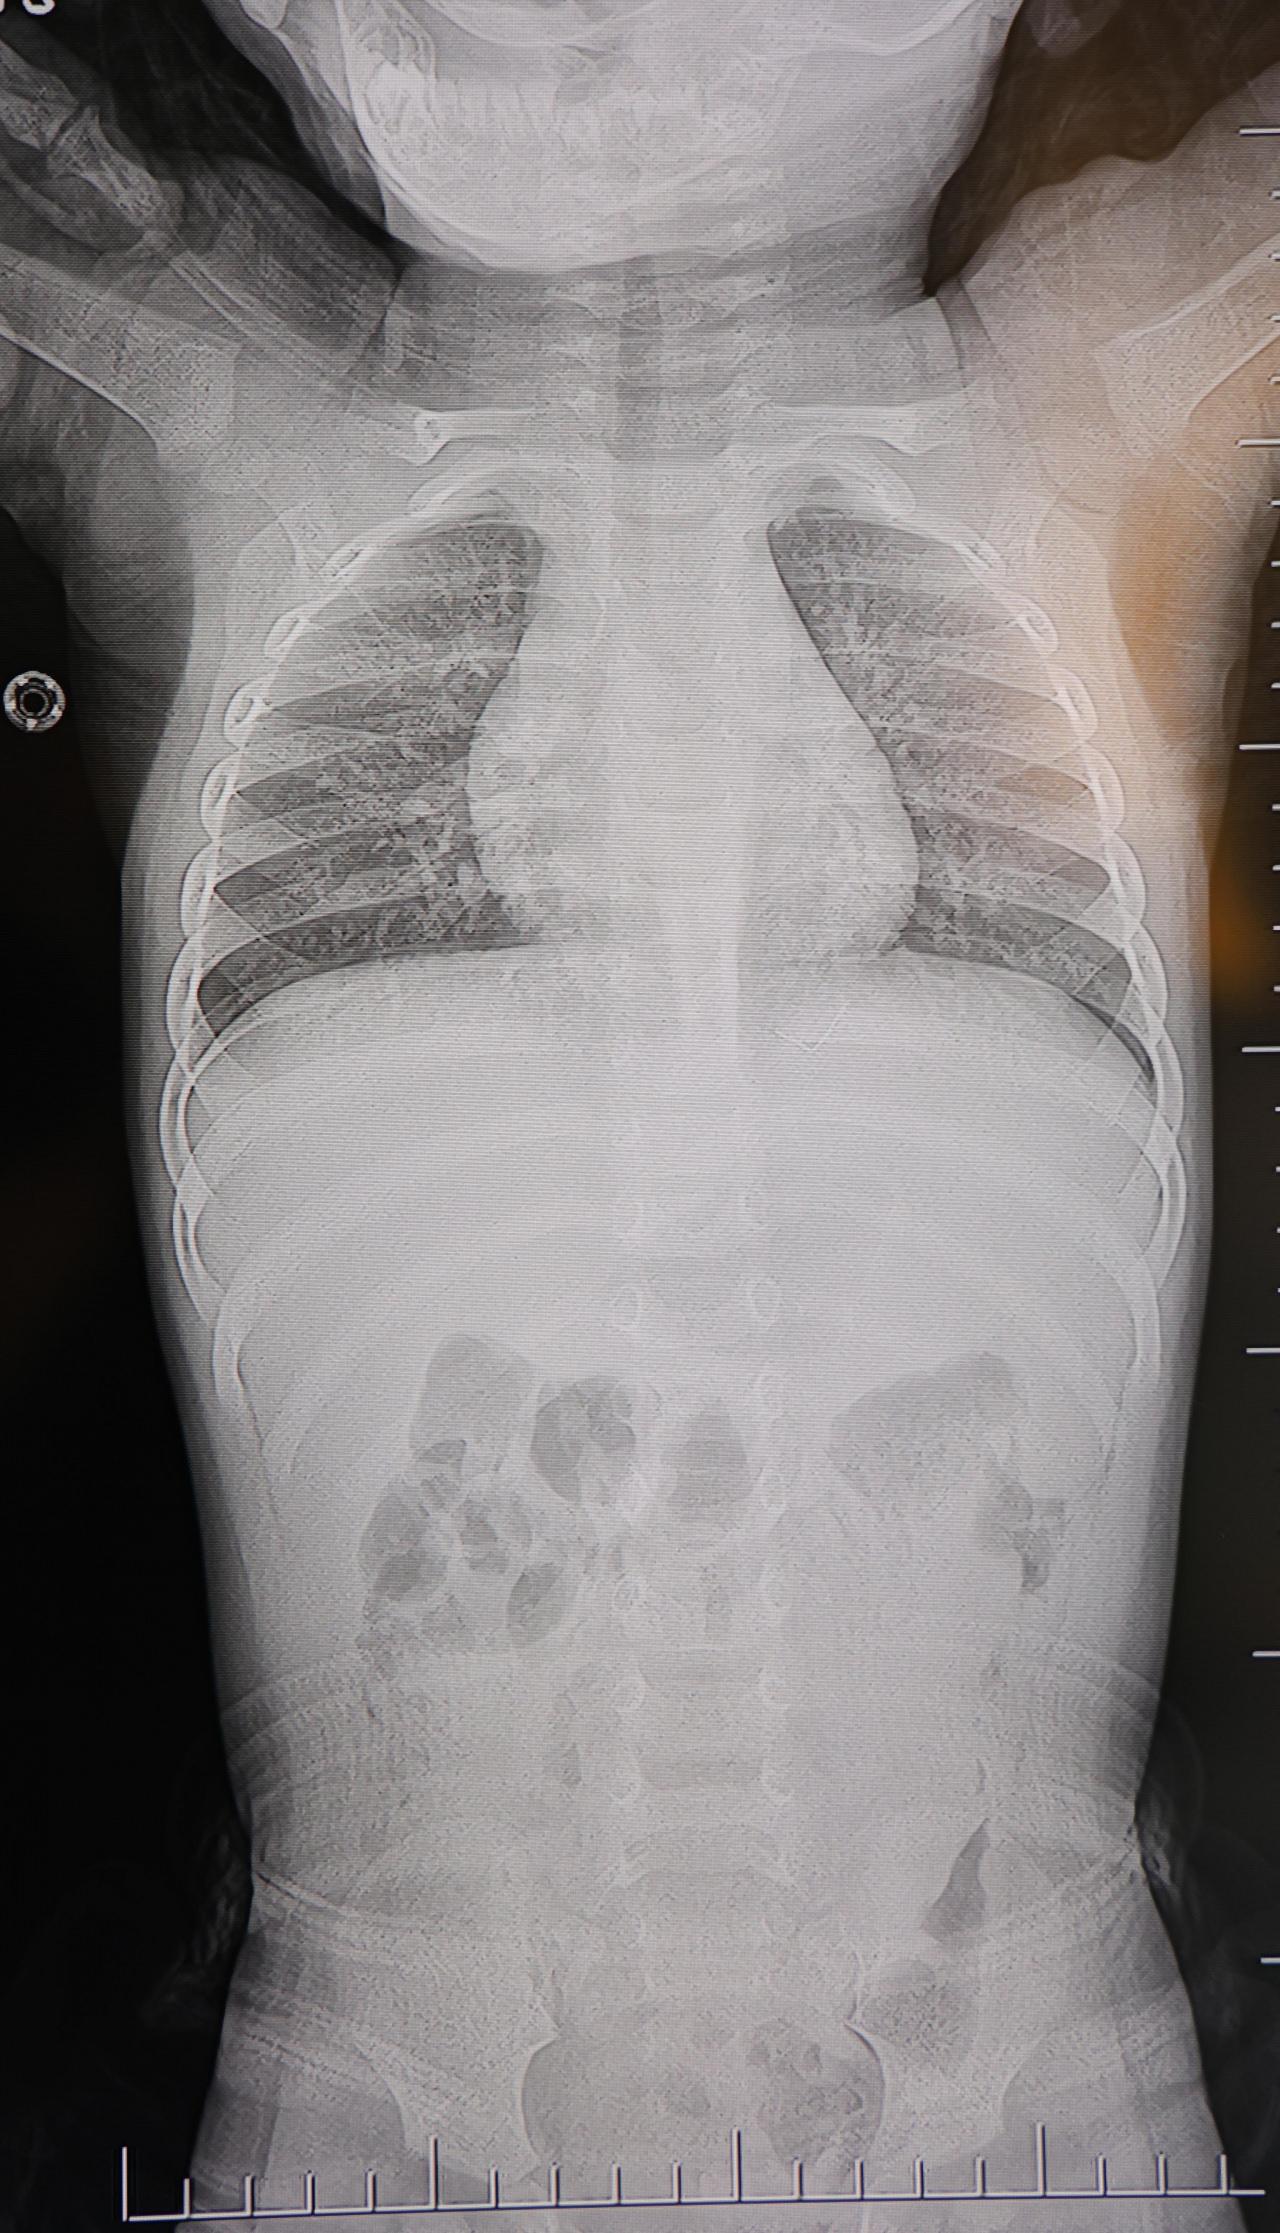

Kahramanmaraş’ta sırt üstü yatmak istemeyen 1 yaşındaki bebeğin sırtında yapılan tetkiklerde, akciğer zarına doğru ilerleyen 2 santimetrelik zımba teli tespit edildi. Yabancı cisim ameliyatla çıkarıldı, bebek aynı gün taburcu edildi.

Aile, bebekleri için son olarak başka bir hastaneye başvurdu. Beyin ve Sinir Cerrahisi Uzmanı Prof. Dr. İdris Altun tarafından yapılan tetkiklerde, yabancı cismin cilt altında, omurilik kanalına yakın bir bölgede olduğu ve akciğer zarına doğru ilerlediği belirlendi. Hasta, genel anesteziye alınmadan, lokal anestezi ve sedasyon eşliğinde ameliyata alındı. Yapılan müdahalede yabancı cisim tamamen çıkarıldı.

Çıkarılan cismin, ince zımba teline benzer metal bir tel olduğu ve yaklaşık 2 santimetre uzunluğunda bulunduğu tespit edildi. Hasta, aynı gün taburcu edildi.

Konuya ilişkin açıklama yapan Prof. Dr. İdris Altun, "Sırtında yabancı bir cisim olduğu söylenmiş ancak çıkarılamayacağı ve 8 yaşına kadar beklenmesi gerektiği ifade edilmişti. Bize başvurduğunda yaptığımız tetkiklerde, cilt altında, omurilik kanalına çok yakın ve akciğer zarına doğru ilerleyen bir yabancı cisim tespit ettik. Hastamızı tamamen uyutmadan, lokal anestezi ve sedasyon eşliğinde müdahale ederek lezyonu tamamen çıkardık. Çıkardığımız cismin ince zımba teline benzer, yaklaşık 2 santimetre uzunluğunda metal bir tel olduğunu gördük.

Bu yabancı cisim alınmasaydı, bölgede enfeksiyon gelişebilirdi. Enfeksiyon sonucu omurilik kanalında ciddi hasarlar oluşabilir, çocuk büyüdükçe cismin hareket etmesine bağlı olarak omurilikte zedelenmeler meydana gelebilirdi.

Ayrıca yana doğru ilerleyerek akciğer zarına ve akciğere batma riski vardı. Bu da enfeksiyona ve ilerleyen süreçte tümörle karışabilecek tablolara neden olabilirdi. Şu an hastamız gayet sağlıklı. Gerekli kontrolleri yaptık ve aynı gün taburcu ettik" dedi.